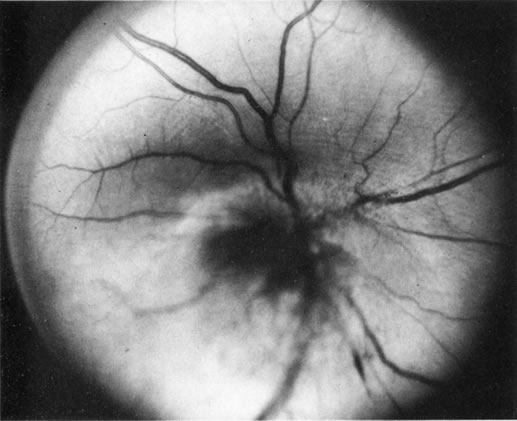

If direct ophthalmoscopy is used, a circumferential peripapillary melanoma can simulate optic neuritis (Fig. 8).

|